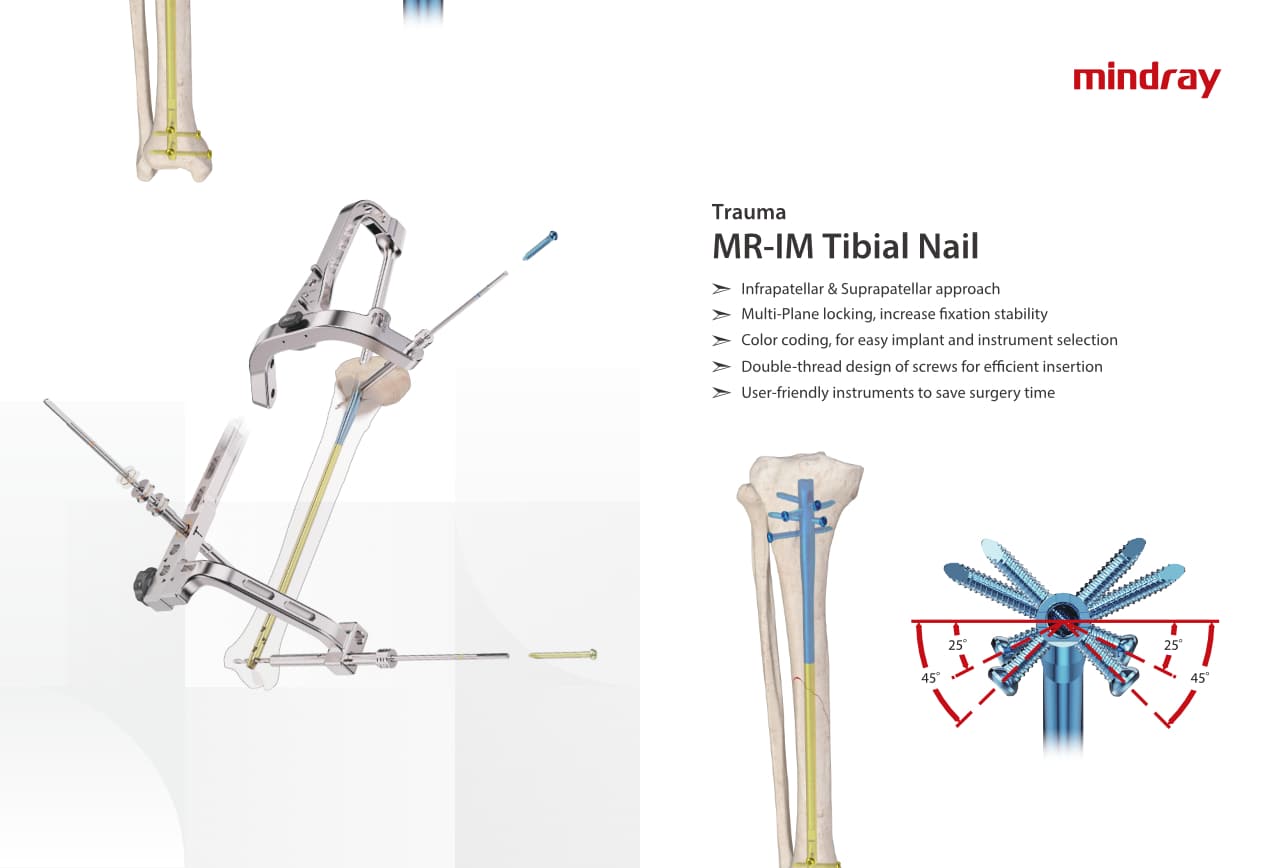

Trauma